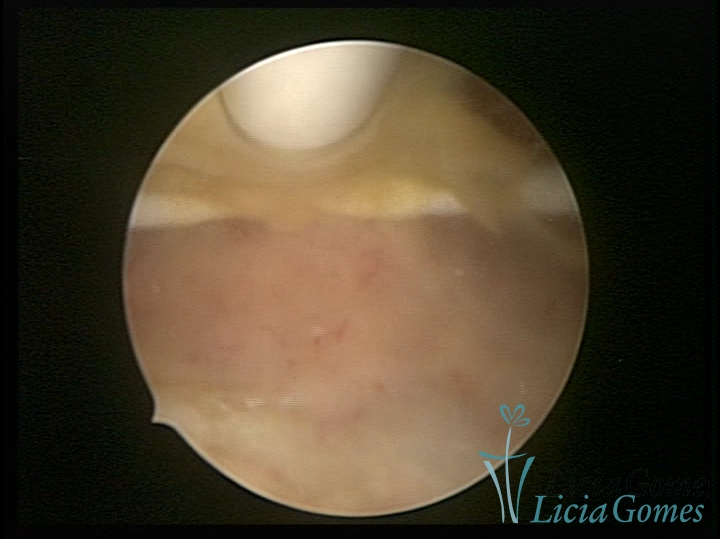

DIU normo inserido

×

Cavidade uterina com DIU normoposicionado